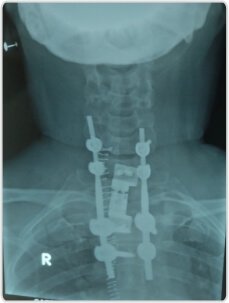

D1, D2 corpectomy with cage fixation এবং posterior cervico-doorsal stabilization অতিরিক্ত সাপোর্টের জন্য সাবস্টারনাল পদ্ধতির মাধ্যমে করা হয়েছিল

ইমপ্লান্ট ব্যর্থতা প্রতিরোধ করতে।

এক্স-রে পোস্ট করুন

এপয়েন্টমেন্ট